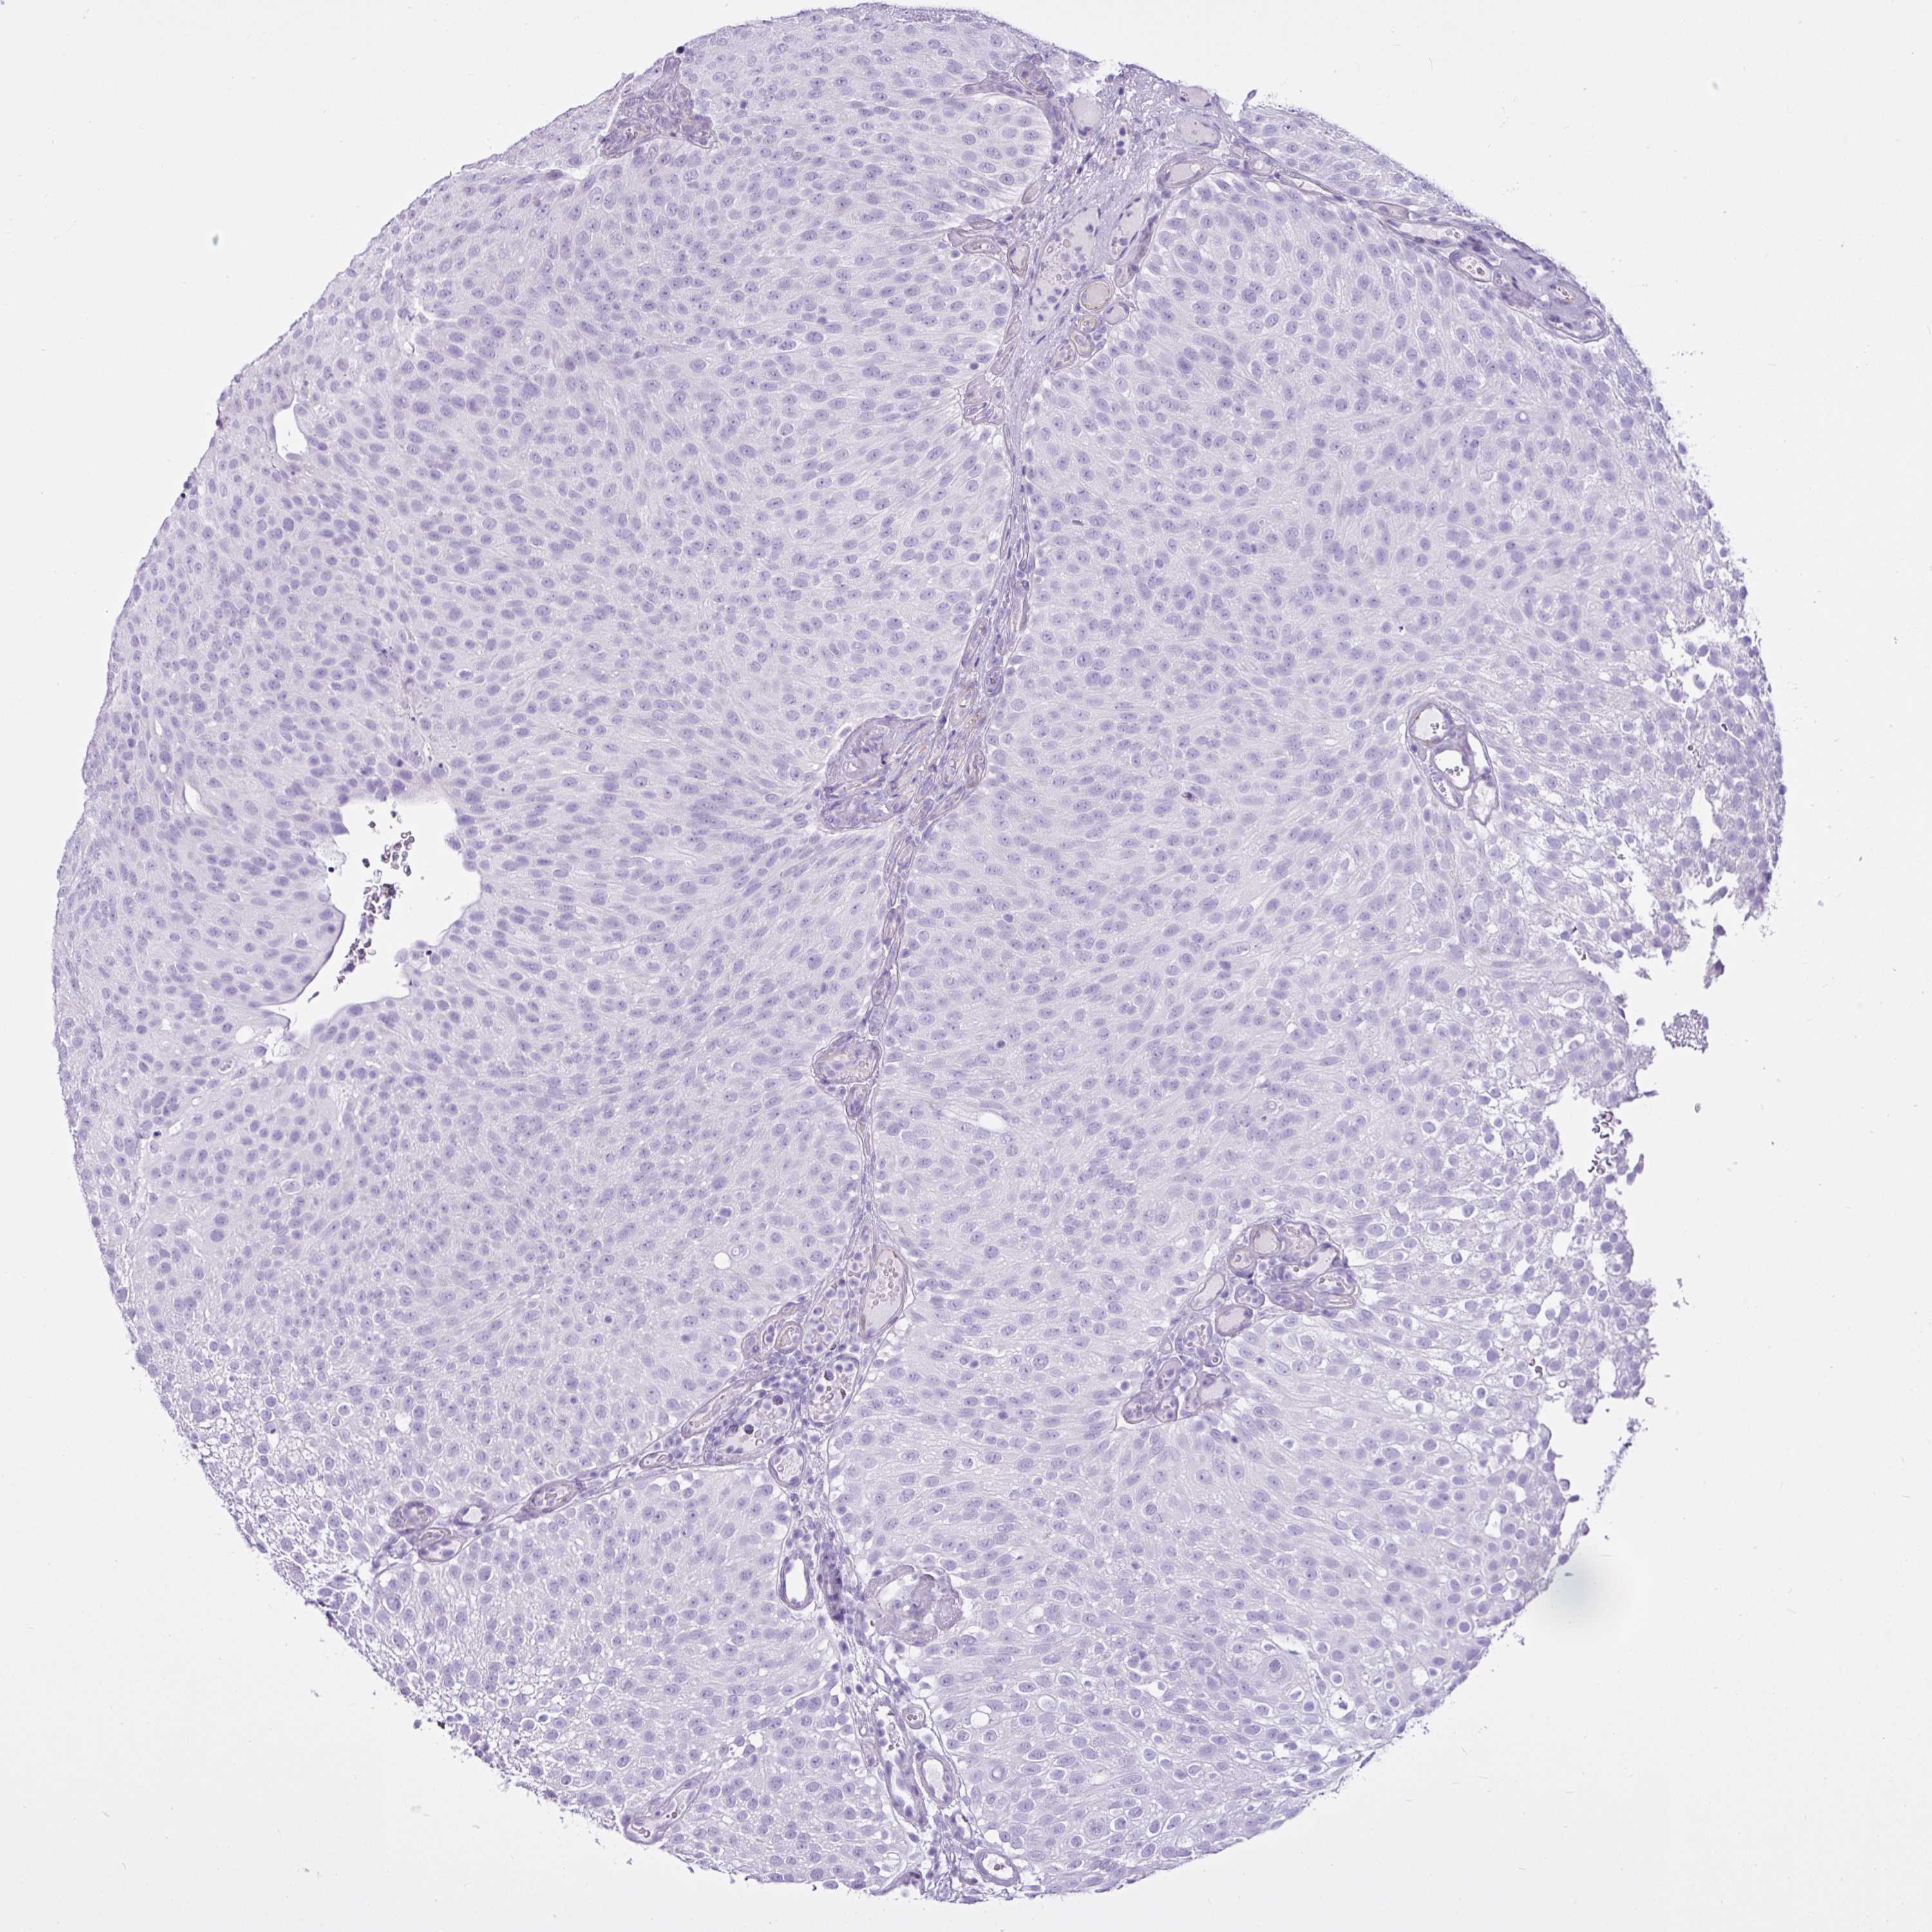

UROTHELIAL CANCER - Protein expressioni

A mouse-over function shows sample information and annotation data. Click on an image to view it in a full screen mode. Samples can be filtered based on level of antibody staining by selecting one or several of the following categories: high, medium, low and not detected. The assay and annotation is described here.

Note that samples used for immunohistochemistry by the Human Protein Atlas do not correspond to samples in the TCGA dataset.

Antibody stainingi

Antibody staining in the annotated cell types in the current human tissue is reported as not detected, low, medium, or high, based on conventional immunohistochemistry profiling in selected tissues. This score is based on the combination of the staining intensity and fraction of stained cells.

Each image is clickable and will lead to virtual microscopy that enables deeper exploration of all samples and also displays staining intensity scores, fraction scores and subcellular localization as well as patient and tissue information for each sample.

Antibody HPA052807

Staining

High

Medium

Low

Not detected

Intensity

Strong

Moderate

Weak

Negative

Quantity

>75%

75%-25%

<25%

None

Location

Nuclear

Cytoplasmic/membranous

Cytoplasmic/membranous,nuclear

Urothelial carcinoma, High grade

Urothelial carcinoma, Low grade

Urothelial carcinoma, NOS